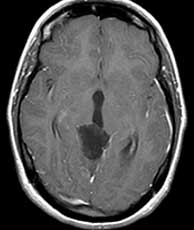

Diagnosis: Vein of Galen malformation

The VOG is the confluence of the basal vein of Rosenthal and the internal cerebral veins. It joins the inferior sagittal sinus to form the straight sinus. The vein of Galen malformation (aneurysm is a misnomer) is an abnormal developmental connection between the VOG and any of the following arteries; anterior cerebrals, anterior and posterior choroidals, lenticulostriates and thalamoperforators. It often presents in the neonatal period with CHF, cranial bruit or seizures. Treatment consists of endovascular embolization and/or surgery. The differential for this case without the angiogram is limited. Perhaps a huge calcified arterial aneurysm or pineal cyst could resemble this. A calcifying pineal region tumor is very unlikely due to the peripheral nature of the calcification. The angio however nails the diagnosis. Related Cases